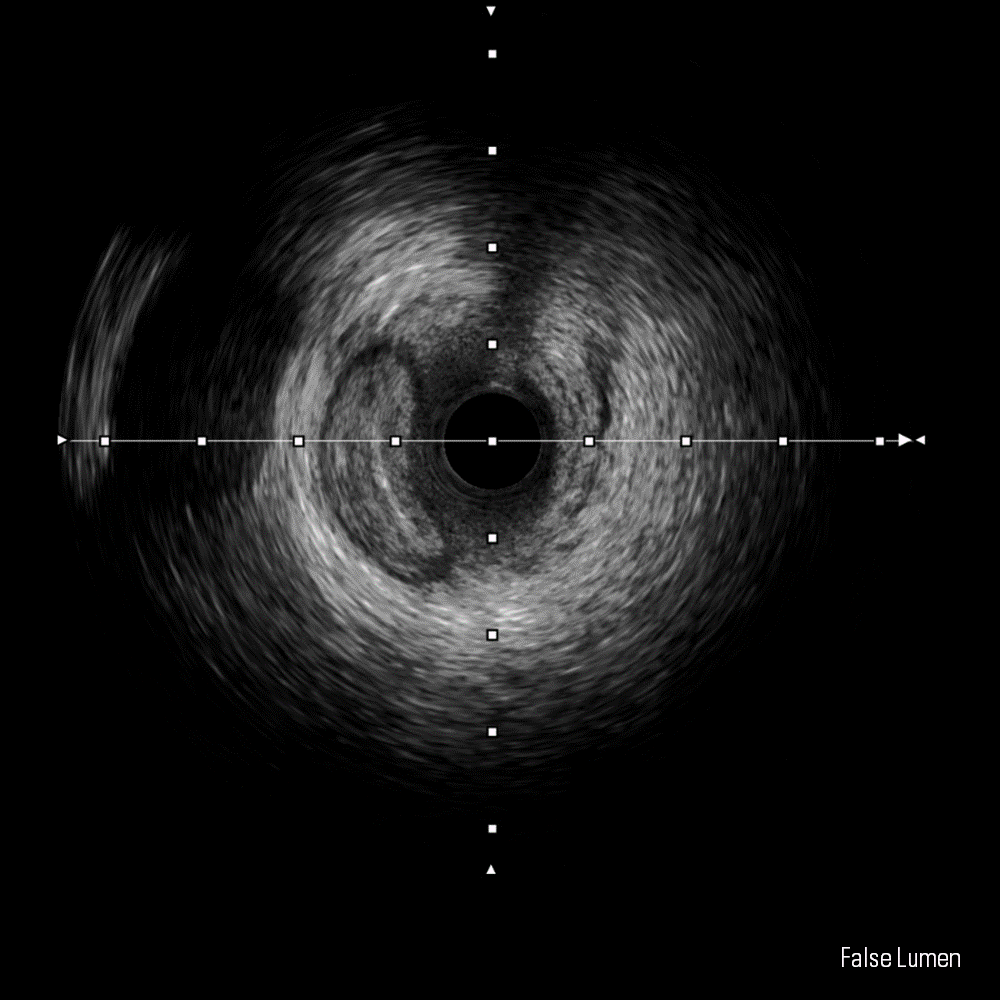

IVUS image for the IVUS image library in Educare

IVUS Image Library

The IVUS image library is a repository of IVUS-guided PCI images including 60 MHz IVUS runs and cross-sectional images, angiograms, and image interpretation tutorials - all available to download.

Dissection, False Lumen and Thrombus images courtesy of Boston Scientific.